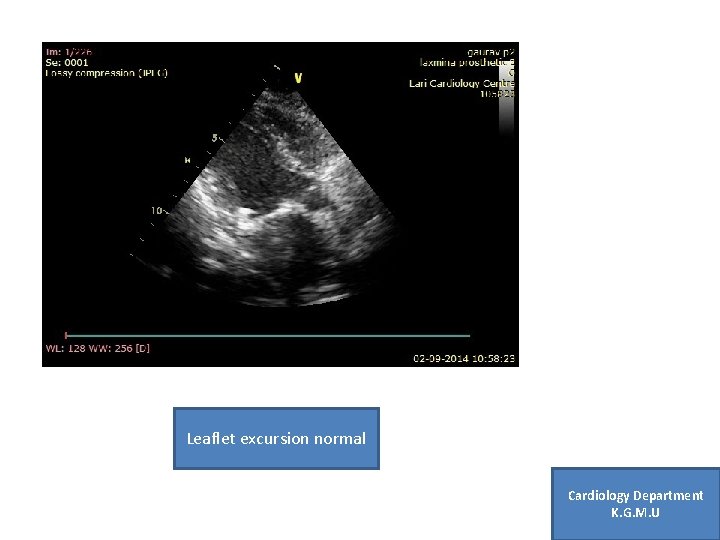

Case 1 1 • 27 yr female , Post MVR (SJM ) 1 yr back Cardiology Department K. G. M. U

Leaflet excursion normal Cardiology Department K. G. M. U